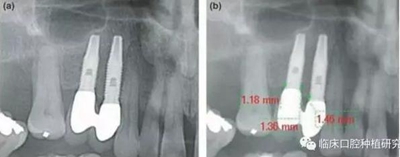

因而,該研究對隨訪達(dá)5年以上的牙列缺損種植修復(fù)患者,進(jìn)行了觀察性縱向回顧性研究。通過影像學(xué)資料對比種植體周圍骨吸收和牙周骨吸收,對其潛在危險因素,如修復(fù)體設(shè)計、口腔衛(wèi)生、植體規(guī)格也進(jìn)行了研究。單變量統(tǒng)計分析結(jié)果發(fā)現(xiàn),性別、種植體系統(tǒng)、拔牙原因、聯(lián)冠修復(fù)、種植體平臺和修復(fù)體間水平距離與種植體周圍骨吸收有顯著相關(guān)性。多變量統(tǒng)計分析結(jié)果發(fā)現(xiàn),性別、種植體系統(tǒng)、拔牙原因、聯(lián)冠修復(fù)、種植體平臺和修復(fù)體間水平距離與種植體周圍骨吸收同樣具有顯著相關(guān)性。其結(jié)果認(rèn)為種植體平臺和修復(fù)體間水平距離對種植體周圍骨吸收負(fù)向影響最大,且這一距離適宜在3.3 mm-6 mm。若超出此范圍,則對種植體周骨吸收不再有影響,但外展隙會逐漸增大,菌斑堆積增多。